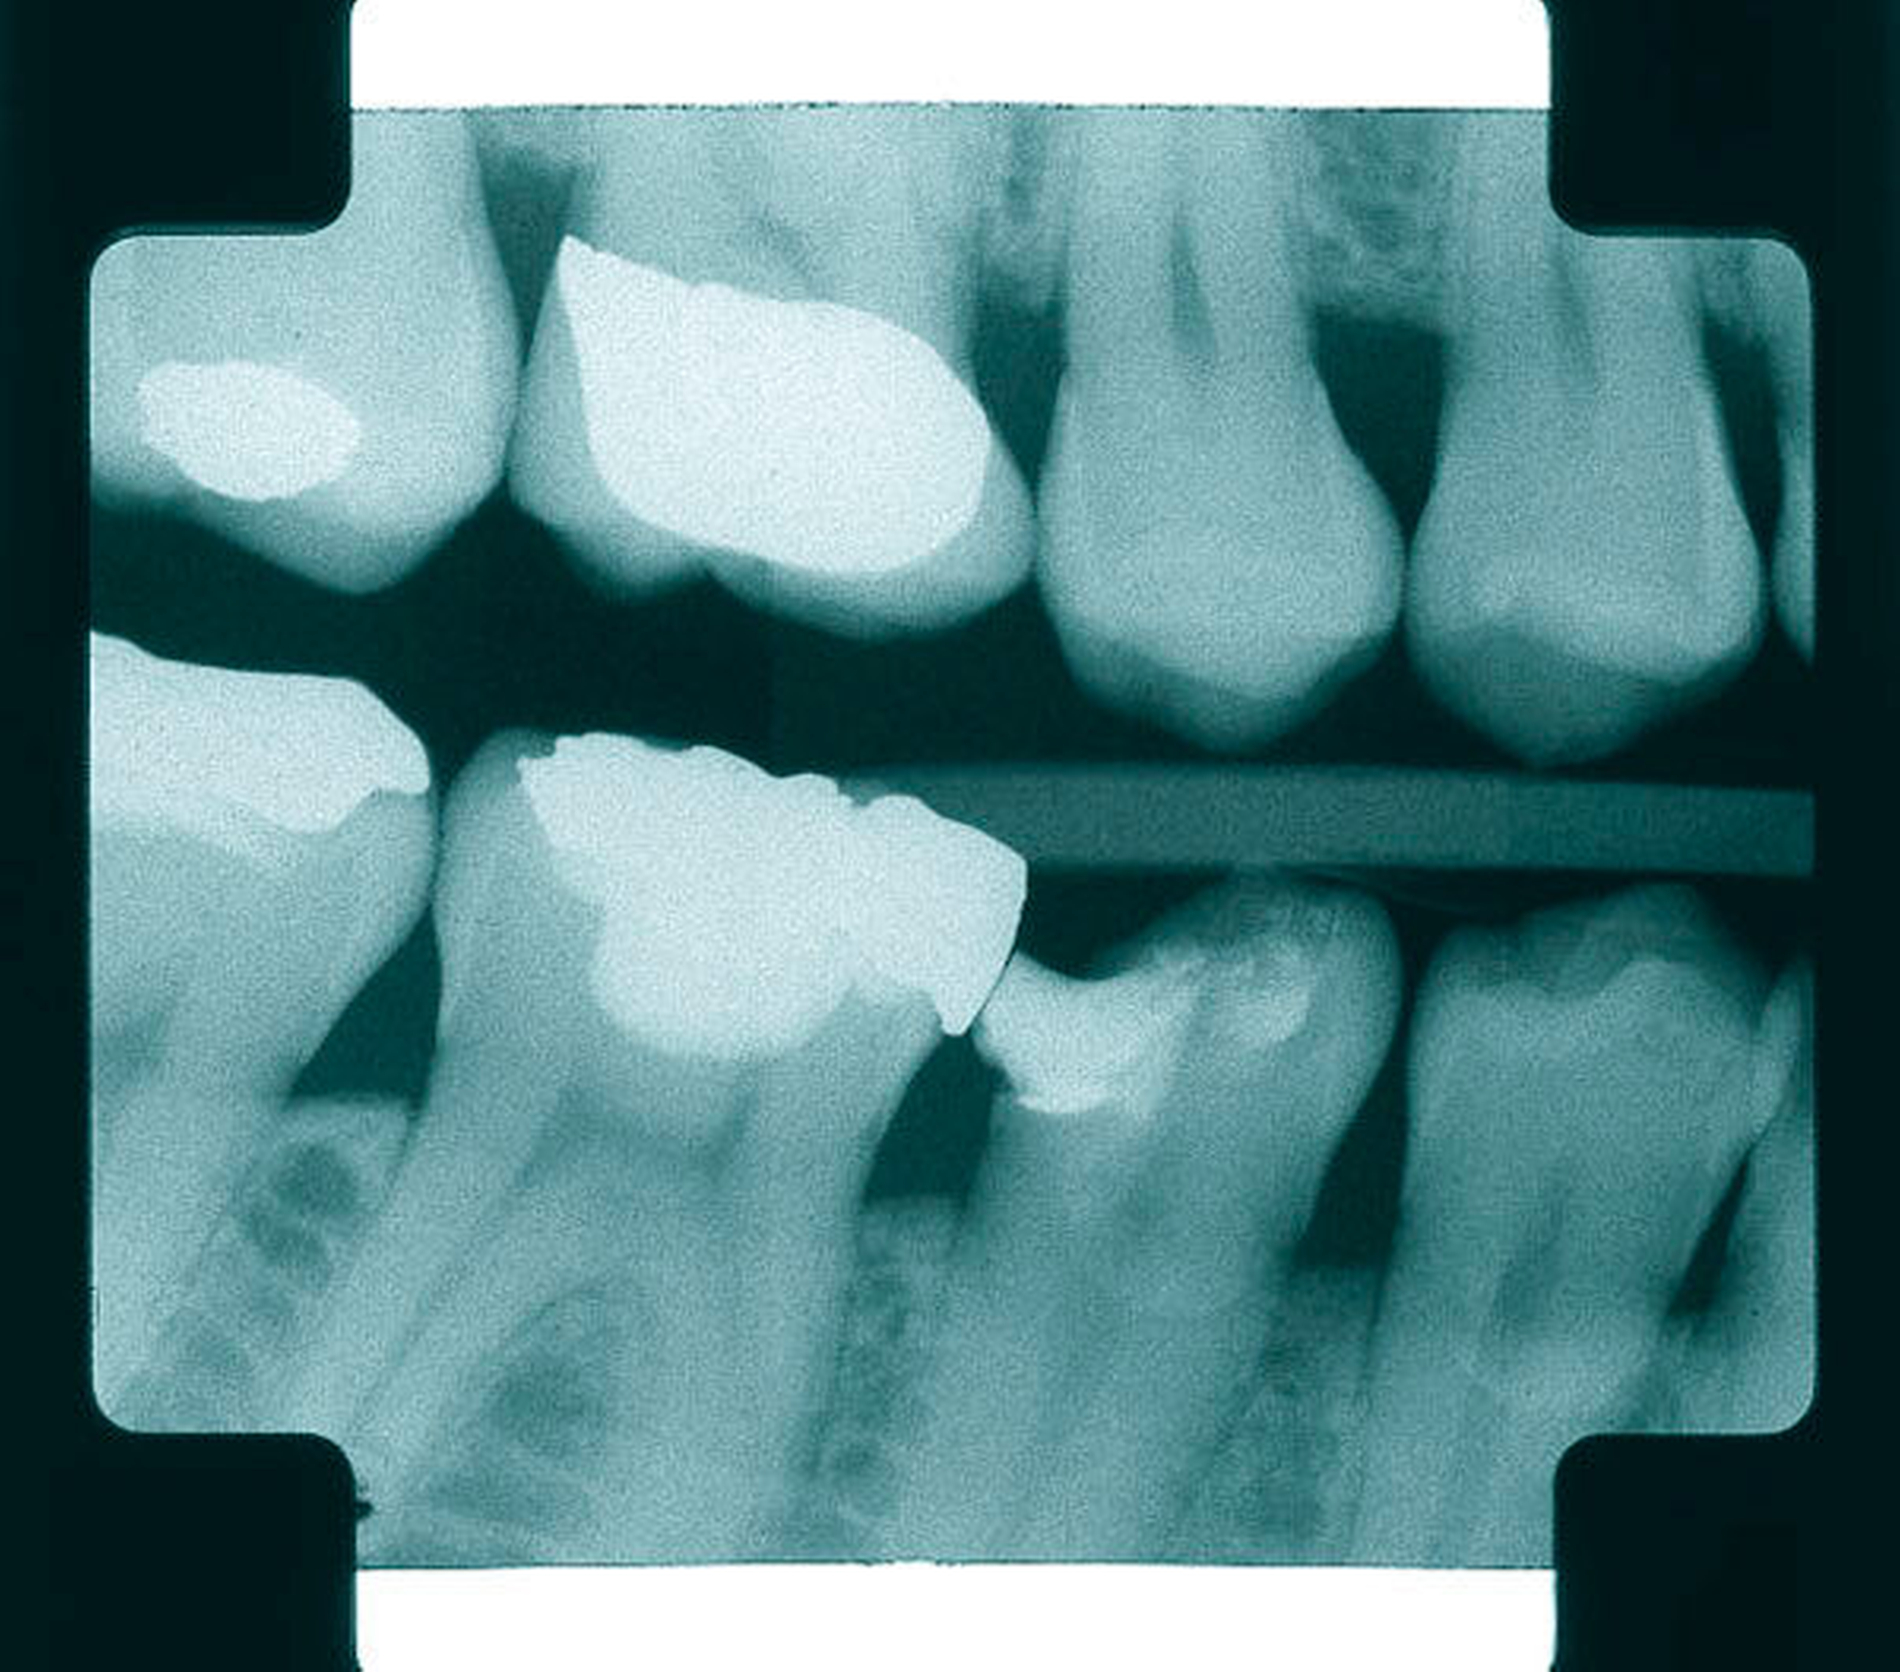

Abbildung 2: Direkte Teilüberkronung im Seitenzahnbereich (R1-Technik)

In den Abbildungen 1 bis 3 werden Optionen für frugale Interventionen auf restaurativem Sektor aufgeführt. Es handelt sich um direkte Vollüberkronungen im Frontzahnbereich (hier: hergestellt in R1-Technik / einphasig) (Abbildung 1), direkte Teilüberkronungen im Seitenzahnbereich (hier: hergestellt in R1-Technik / einphasig) (Abbildung 2), Reparatur-Restaurationen im Seitenzahnbereich (hier: hergestellt in R2-Technik / zweiphasig) (Abbildung 3). Technische Einzelheiten zur Vorgehensweise und den Ergebnissen sind an anderer Stelle beschrieben (Literatur siehe oben).

Für die in Abbildung 2 dargestellte Situation eines tief zerstörten Prämolaren gelten ähnliche Charakteristika. Es gibt in der restaurativen Zahnheilkunde viele Neuerungen, die das Behandlungsspektrum vergrößert haben. Dazu zählen unter anderem:

ein- oder zweiphasiges Vorgehen je nach Defektausdehnungen (R1- und R2-Technik),

von Präparationsgrenzen unabhängige Verschalungstechniken, die auch bei nicht-kariesbedingten Zahnhartsubstanzschäden (wie etwa Hypomineralisationen) zum Einsatz kommen können,

schadensgerechte Reparaturtechniken (Abbildung 3),

neuartige Insertionstechniken, die unter anderem die Anpassung neuer Restaurationen an vorhandene prothetische Versorgungen (Reziproktechnik) erlauben.